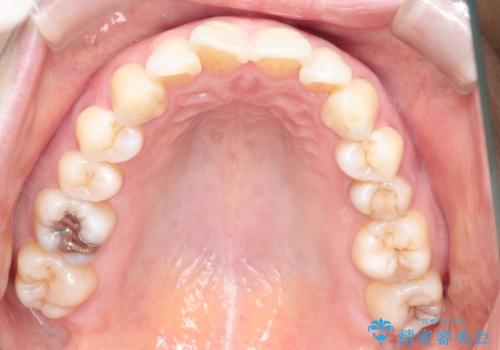

審美装置を用いたワイヤー矯正|非抜歯で歯の凸凹を改善

- 患者様は**歯の凸凹(叢生)**を気にされて来院されました。診査の結果、歯列のスペースが不足しているものの、抜歯をせずに改善できる状態でした。そこで、目立ちにくい審美装置(白いブラケットとホワイトワイヤー)を使用したワイヤー矯正を提案しました。歯列のアーチを広げながら、適宜IPR(歯の幅をわずかに調整する処置)を行い、非抜歯で自然な歯並びへと導く計画を立てました。

治療では、白いブラケットとホワイトワイヤーを使用し、矯正装置が目立ちにくいよう配慮しました。歯列を拡大しながら適切に歯を移動させ、IPRを併用することで、無理なくスペースを確保しました。見た目に配慮しながら、歯の凸凹をスムーズに整え、噛み合わせも改善。患者様からは「装置が思ったより目立たず、歯並びがきれいになって嬉しい」との声をいただきました。